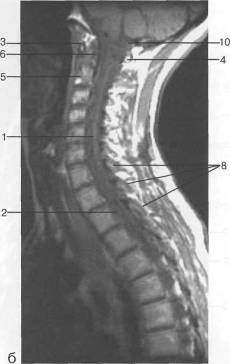

Рис. 12. МРТ. Срединное

сагиттальное изображение шейного отдела позвоночника. а-Т2-ВИ;б-Т1-ВИ.

- спинной мозг; 2 -

субарахноидальное пространство; 3 - дуральный мешок (задняя стенка); 4 -

эпидуральное пространство; 5 - передняя дуга С1; 6 - задняя дуга С1; 7 - тело

С2; 8 - межпозвонковый диск; 9 - гиалиновая пластинка; 10 - артефакт

изображения; 11 - остистые отростки позвонков; 12 - трахея; 13 - пищевод.